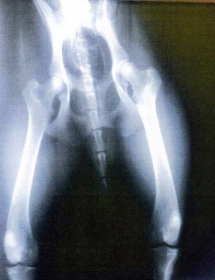

Durante a consulta, ele teria analisado um raio-X de um cachorro, que havia sido entregue pelo policial, e não percebeu a diferença entre a radiografia do cão e a de um homem.